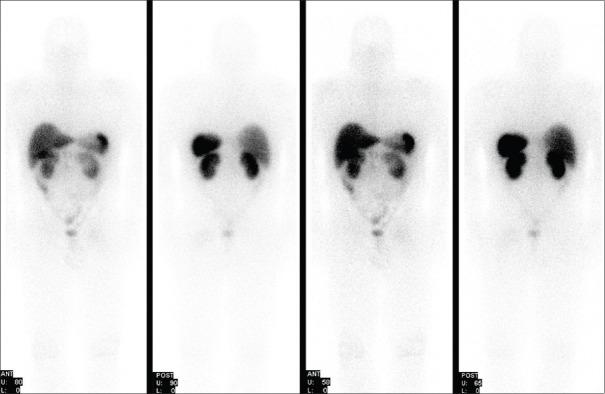

Ga-DOTATATE positron emission tomography/computed tomography (PET/CT) has shown superiority over Indium-octreotide scanning for the detection of phosphaturic mesenchymal tumors (PMTs). We report a case of tumor-induced osteomalacia resulting from PMT which, although initially clinically suspected, was not localized on octreotide scintigraphy performed several years prior. Subsequent surgical excision of a presumed benign osseous lesion a few years later revealed the diagnosis on pathology. Imaging assessment using Ga-DOTATATE PET/CT following recent clinical suspicion for recurrence revealed an intense tracer-avid lesion at the primary tumor site. DOTATATE imaging plays an important role in localizing tumors with high somatostatin receptor expression, such as neuroendocrine tumors (pheochromocytoma, paraganglioma, and neuroblastoma), meningioma, and mesenchymal tumors, causing oncogenic osteomalacia.

镓标记的生长抑素类似物正电子发射断层扫描/计算机断层扫描(PET/CT)在检测磷酸尿性间叶肿瘤(PMT)方面已显示出优于铟标记的奥曲肽扫描。我们报告一例由PMT引起的肿瘤性骨软化症病例,尽管最初临床上怀疑有该疾病,但在数年前进行的奥曲肽闪烁扫描中未发现其定位。几年后对一个推测为良性的骨病变进行手术切除,术后病理检查明确了诊断。最近临床怀疑复发后,使用镓标记的生长抑素类似物PET/CT进行影像学评估,结果显示在原发肿瘤部位有一个摄取示踪剂强烈的病变。生长抑素类似物成像在定位具有高生长抑素受体表达的肿瘤方面发挥着重要作用,这些肿瘤包括神经内分泌肿瘤(嗜铬细胞瘤、副神经节瘤和神经母细胞瘤)、脑膜瘤以及导致肿瘤性骨软化症的间叶肿瘤。